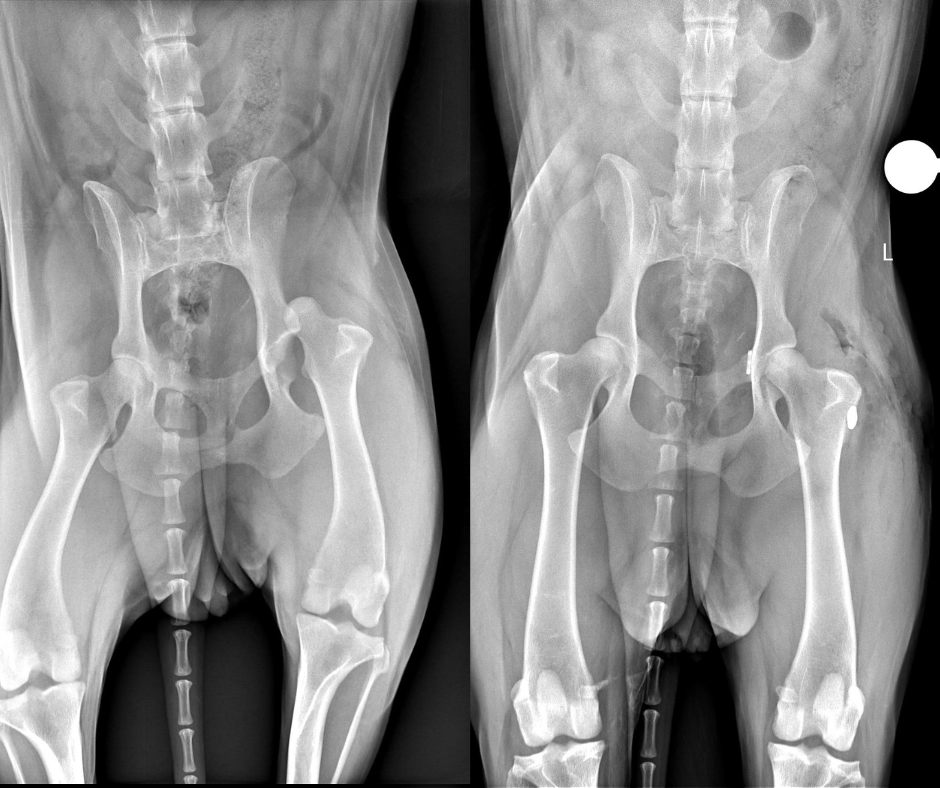

Fristoe raced to nearby Wellington Veterinary Hospital, where X-rays revealed Maisie Mae was leaking air into her chest and fluids into her abdomen. The vets stabilized her and called ahead to CSU’s James L. Voss Veterinary Teaching Hospital, where the emergency room staff was waiting for her.

Maisie Mae was alive, with a broken rib, and dislocated hip, but the blood loss and trauma to her lungs were life-threatening.

Her hip was popped back into place under sedation “but it re-luxated, so we took her to surgery and surgically stabilized the hip,” said Dr. Clara Goh, the CSU orthopedic surgeon who performed a toggle procedure on Maisie’s hip joint. “It’s essentially a prosthetic ligament to hold the joint in place, and she orthopedically recovered very well.”

Two weeks after the surgery, Maisie Mae returned to the hospital for a checkup, her “comfort duckie” in tow. Dr. Joey Sapora of the Small Animal Orthopedic Surgery service removed Maisie Mae’s sutures and assessed her range of movement. “She looks really strong for two weeks out, but she will need to be mellow for at least another four to six weeks,” he told Fristoe.